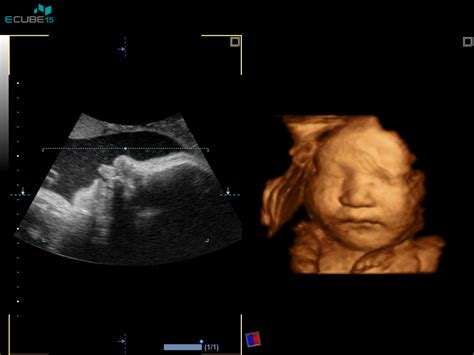

- Ultrazvočni pregled: Večinoma se uporablja vaginalna sonda za natančnejšo oceno zgodnje nosečnosti. Z ultrazvokom se potrdi, da se nosečnost razvija v maternici, izključi se možnost zunajmaternične nosečnosti, določi se število plodov in oceni njihova velikost (dolžina od temena do trtice - TT). Ta meritev omogoča preverjanje točnosti datuma poroda, določenega glede na zadnjo menstruacijo. Če odstopanje presega 7 dni, se predvideni datum poroda (PDP) prilagodi glede na ultrazvočno meritev.